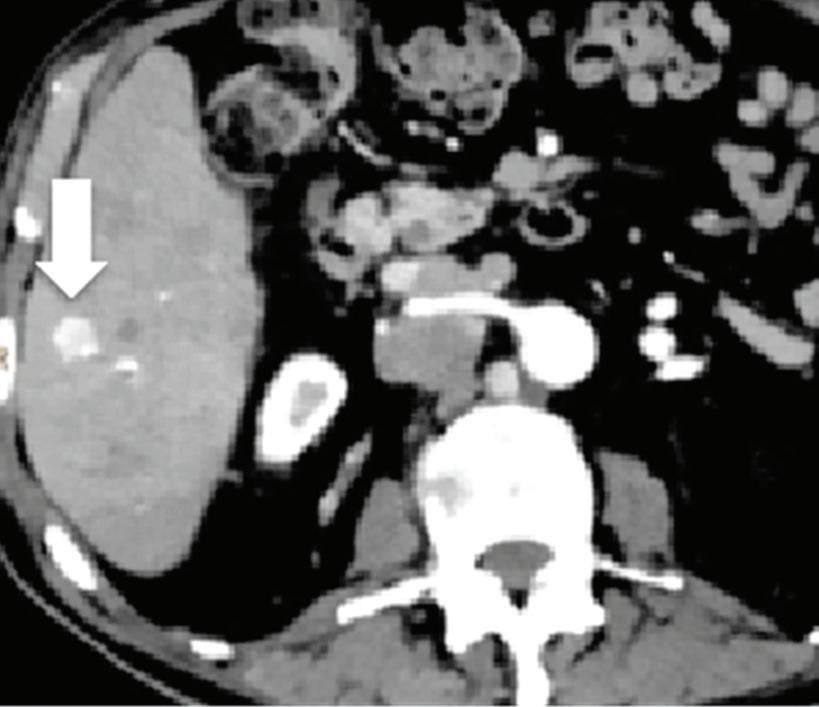

Renal and adrenal gland tumors. Contrast-enhanced-DECT images are particularly useful for the characterization of incidental renal or supra-renal lesions and for their follow-up, without the need of conventional unenhanced acquisition, translating into achieving a 30% mean dose savings for triphasic and up to 50% for biphasic renal protocols in daily clinical practice.17 It is also very useful in depicting hypervascular renal cell carcinoma metastasis in the liver or other sites, such as in the peritoneum and bowel wall (Figures 2 and 3).

Effectiveness of spectral CT imaging for detection of hypervascular liver metastases. A small hypervascular metastasis (arrow) from renal cell carcinoma. (a) Axial contrast-enhanced conventional CT image obtained in the arterial phase, corresponding (b) monoenergetic 50 keV, and (c) Z effective image.